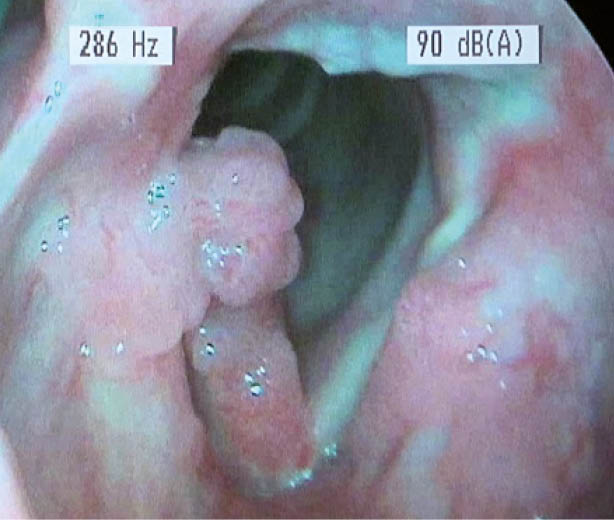

Larynxpapillomatose (Abb. 4):

Diese virale Kehlkopferkrankung, verursacht durch Humane Papillomaviren (HPV), kann in jedem Alter auftreten. Auf den Stimmlippen sind kleine Papillome mit himbeerartigem Charakter erkennbar. Eine Biopsie ist empfehlenswert, einerseits mit Frage nach Virustyp (6 und 11 gehören zur «Low-Risk-Gruppe» für Malignitätspotenzial, 16 und 18 gehören dagegen zur «High-Risk-Gruppe»), anderseits mit Frage nach bereits vorhandenen Dysplasien.